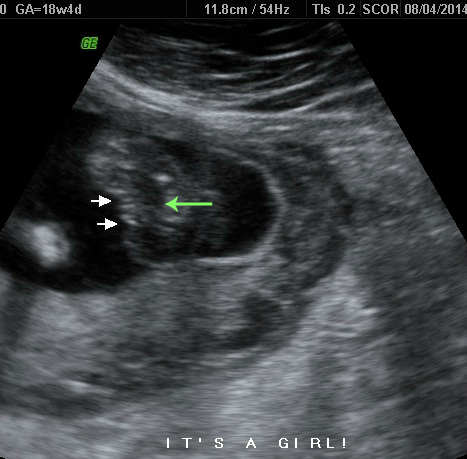

I see the three white lines, but I see a little, very faint sideways 'y' with the middle line in the middle of it. I see the sideways 'y' on some girl potty shots, but usually it's part of the three lines and not in addition? Any ideas what I'm looking at? It just has me confused.

Attachment 20331

Gestation - between 18w and 19w